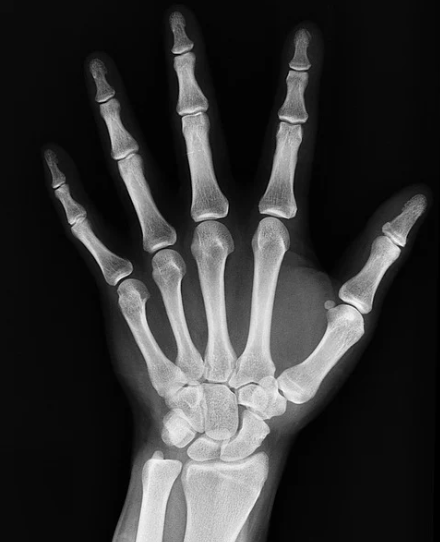

뼈에 금이 갔을때 증상 - 통증

뼈에 금이 가게되면 생각만 해도 엄청 아플것 같은데 그 증상 중 당연하게 통증이 포함되어 있습니다. 개개인 마다 통증의 정도는 다르겠지만 뼈에 금이 간경우 대부분은 통증이 가라앉지 않고 계속 지속되거나 더한 통증을 느낀다고 합니다. 또한 금이 간 곳에 압력을 가하거나 움직이는 등의 무리한 행동을 한다면 더욱 심한 통증이 느껴지고 그 주위에 있는 다른 장기들 까지도 통증이 느껴지거나 손상이 될 수도있다고 합니다. 통증은 저린느낌이나 쑤시는 느낌등 다양하게 나타날 수있으니 어느 특정 부위에서 계속해서 통증이 느껴진다면 병원에 가서 진료를 받아보시는게 좋습니다.